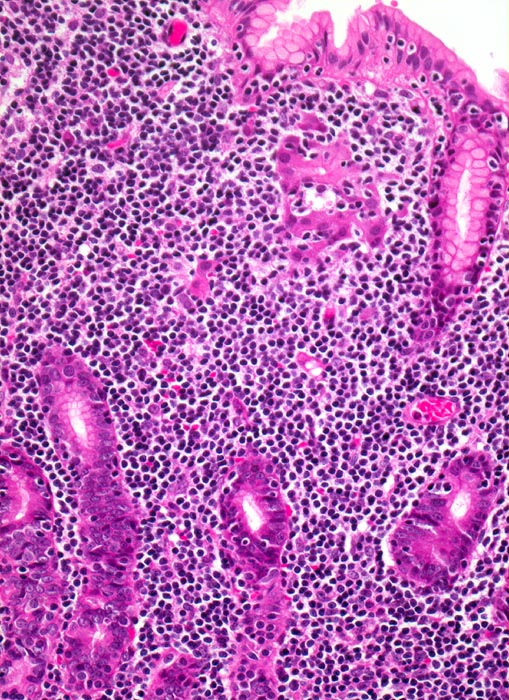

extranodales Marginalzonenlymphom vom MALT-Typ

Magenantrum

Monomorphes kleinzelliges Lymphominfiltrat in der Antrummukosa. Die Lymphomzellen infiltrieren die Drüsenschläuche und zerstören diese. Die Monomorphie des Infiltrates und das Übergreifen auf das Magenepithel erlauben die Abgrenzung von einer chronischen Gastritis.

73 jährige Patientin mit chronischer Helikobakter-Gastritis. Magenbefall ohne Lymphknotenbefall.